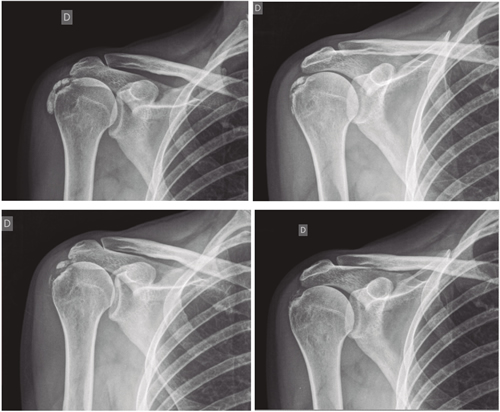

El número promedio de sesiones en nuestra serie fue de 20. El criterio para continuar o suspender el tratamiento fue la evolución radiológica y clínica (Figuras 4 y 5). Las intervenciones se realizaron hasta un máximo de 40 sesiones. Perrón trató a sus pacientes por 9 sesiones (3 sesiones semanales por 3 semanas) (14). Leduc trató con 10 sesiones (3 por semana las dos primeras semanas; y luego una semanal por 4 semanas) (15). Rioja-Toro trató a sus pacientes por 40 sesiones (5 veces por semana) y los evaluó a las 20 y a las 40 sesiones (3). Chico-Álvarez trató a sus pacientes entre 15 y 30 sesiones dependiendo de la evolución radiológica (5 veces por semana) (1).

Fig. 4. Paciente mujer de 47 años con tendinitis calcificante de supraespinoso derecho, de tipo formativa, quien tras 30 sesiones de iontoforesis disminuyó el dolor medido por EVA de 6/10 a 3/10 y la calcificación de 38 mm a 8 mm (valoraciones al inicio, a las 10, a las 20 y a las 30 sesiones, respectivamente).